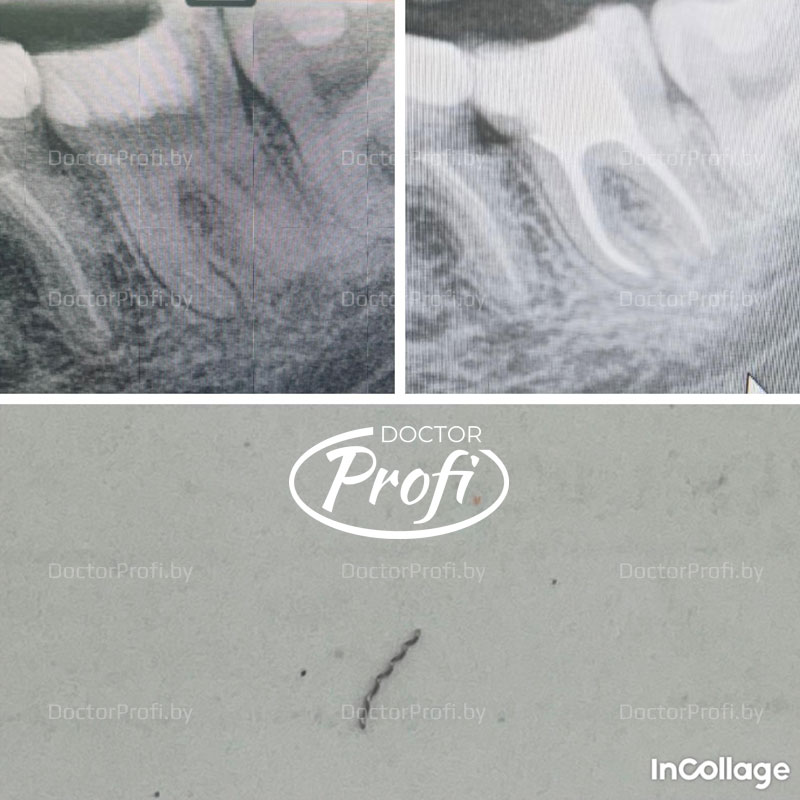

Пациентка С. направлена из другой клиники для извлечения фрагментированного инструмента (каналонаполнителя).

Работа проводилась под визуальным контролем с помощью операционного микроскопа, извлечён фрагмент инструмента. Далее пациентка пожелала продолжить лечение в нашей клинике. Корневые каналы обтурированы методом вертикальной компакции гуттаперчей, проведена окончательная реставрация.